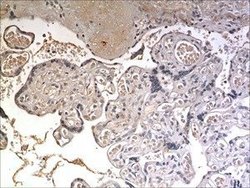

Supportive validation

- Submitted by

- antibodies-online (provider)

- Main image

- Experimental details

- Image(s): Immunohistochemistry